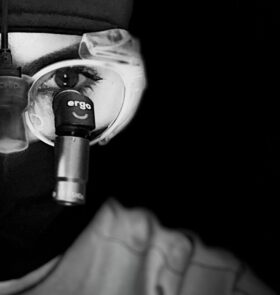

Trabajamos con lupas de magnificación de alta potencia que nos permiten ver detalles microscópicos. Esto garantiza tratamientos más precisos, conservadores y resultados más predecibles en el tiempo.